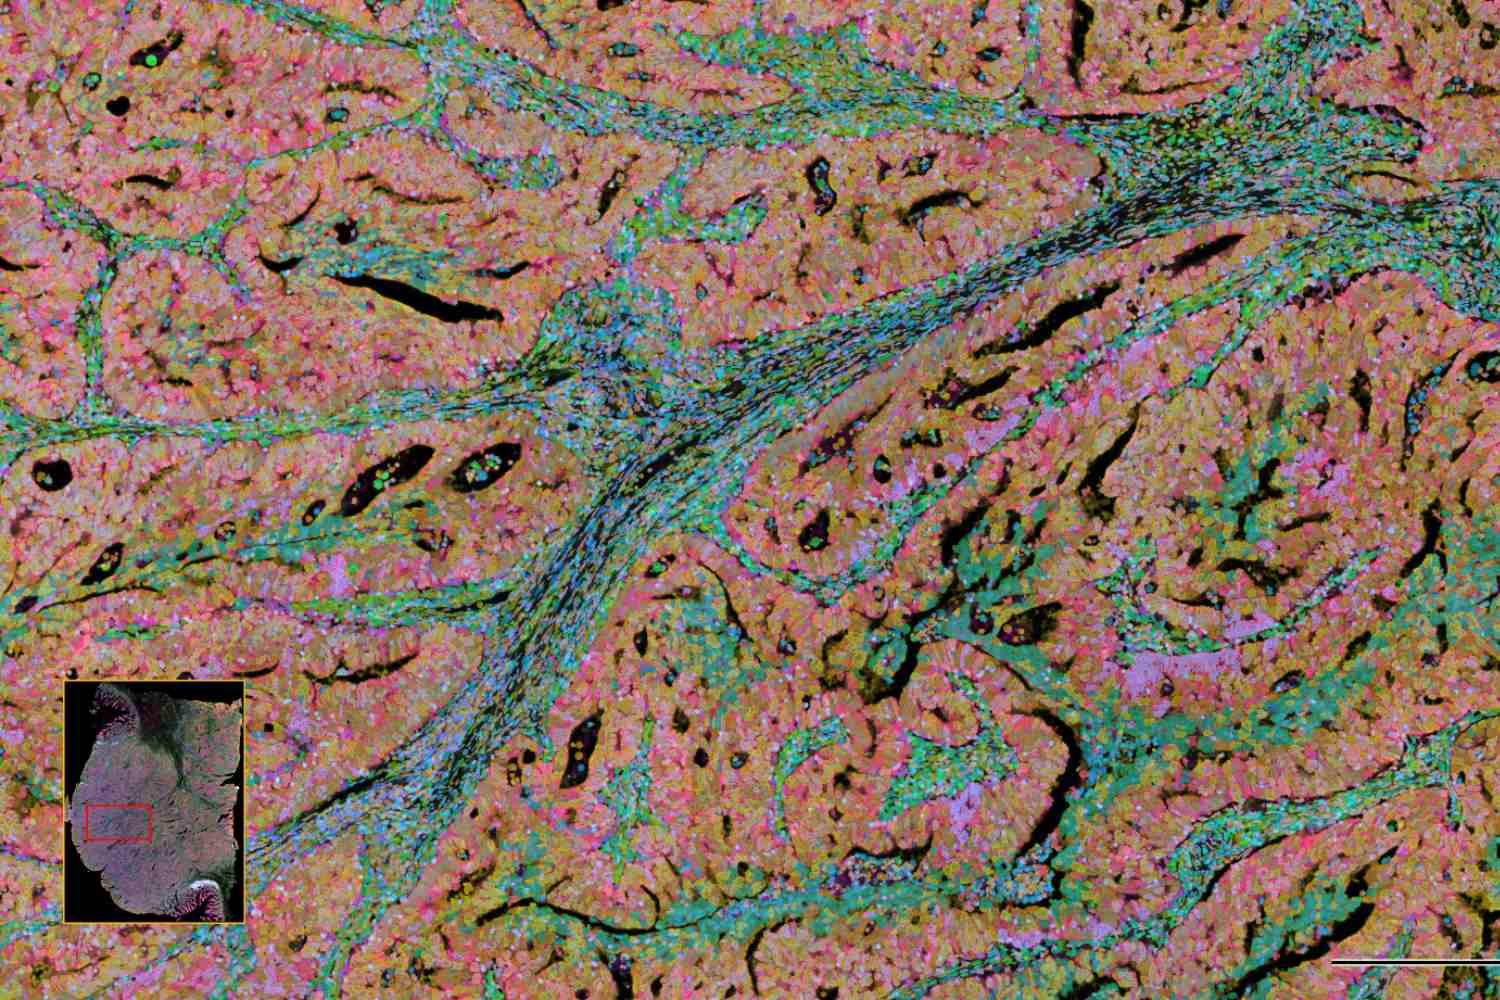

Según señala Luis Martí-Bonmatí, ex presidente de la SERAM, académico de Número de la Real Academia de Medicina de España y director de área clínica de Imagen Médica del Hospital Universitario y Politécnico La Fe de Valencia, "la IA ha irrumpido con fuerza en la radiología abdominal prometiendo una transformación profunda: detección más ágil, flujos de trabajo optimizados y una mejora global en la calidad diagnóstica". Sin embargo, pese a sus avances técnicos y unos beneficios que parecen tan claros en la mejora de la eficiencia, precisión y estandarización de los informes radiológicos, "su adopción en la práctica asistencial diaria sigue estando limitada" por barreras tecnológicas, metodológicas y de integración de los propios profesionales en los circuitos.  En su opinión, "si los radiólogos no participan realmente en la toma de decisiones, si no se armonizan los criterios de evaluación tecnológica y clínica, los modelos que se implementen no serán robustos ni lograrán resultados clínicamente fiables y generalizables".

Para el especialista, la IA ofrece ventajas en la reducción de tiempos de informe, aumento de la sensibilidad diagnóstica, mejora de su reproducibilidad, reduciendo la variabilidad interobservador, y estandarización del proceso radiológico, desde la adquisición hasta el informe final. En oncología, donde el seguimiento mediante imagen es un pilar fundamental, "estas capacidades son especialmente relevantes". La IA permite una evaluación longitudinal, multimodal y multiorgánica, mejorando la monitorización de la progresión tumoral y la respuesta al tratamiento. Por todo ello, expone, "existen ya múltiples escenarios donde la IA está demostrando valor: esteatosis hepática (cuantificación automática y reproducible), carcinoma hepatocelular (caracterización), cáncer de próstata (segmentación glandular y mejora en la detección de lesiones clínicamente significativas) y evaluación de respuesta tumoral (RECIST, mediciones automáticas y seguimiento longitudinal)". La IA aplicada a la radiómica añade variables como textura, realce o cambios en el tiempo (delta-radiomics), "ampliando la evaluación más allá del tamaño tumoral".